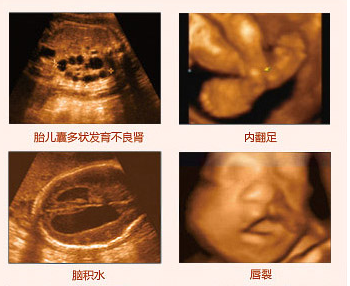

四維彩超排畸圖像

莆田盛興醫(yī)院引進(jìn)的美囯GE四維彩超,擁有當(dāng)今超聲發(fā)展較前沿的技術(shù),拓展了超聲臨床應(yīng)用范圍。美囯GE四維彩超能夠多方位、多角度地觀察宮內(nèi)胎兒的生長(zhǎng)發(fā)育情況,為早期診斷胎兒先天性體表畸形和先天性心臟疾病提供準(zhǔn)確的科學(xué)依據(jù)。不僅能夠發(fā)現(xiàn)體表畸形,同時(shí)能夠?qū)崟r(shí)的觀察人體內(nèi)部器官的動(dòng)態(tài)運(yùn)動(dòng)。可以檢測(cè)和發(fā)現(xiàn)各種異常,從血管畸形到遺傳性綜合征等。推選閱讀 四維彩超可以排查胎兒哪些畸形